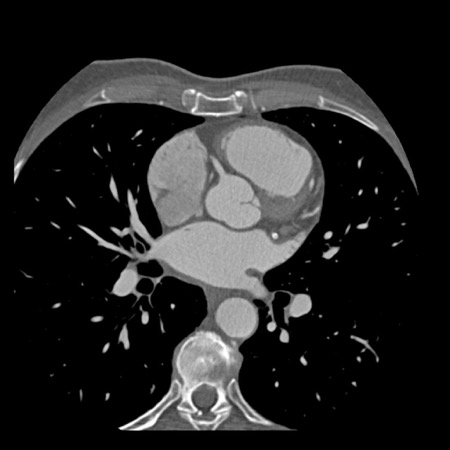

case 1 – CAD-RADS 2/P1

First, scroll through the scan.

Not all images are included. Some images without any abnormalities are skipped

from the series.

How would you describe the findings on the coronary CTA?

The findings are:

- Agatston score of

this patient was 14 (P1). Please, also note the calcification of the aortic valve. - Some partially

calcified and calcified plaques are present in the LAD with mild stenosis

(25-49%). - Calcified-plaque in

the LCX causing minimal stenosis (<25%). - Non-calcified

plaque in the distal RCA causing minimal stenosis (<25%). - This patient classifies

as CAD-RADS 2/P1, which means no further workup is needed.